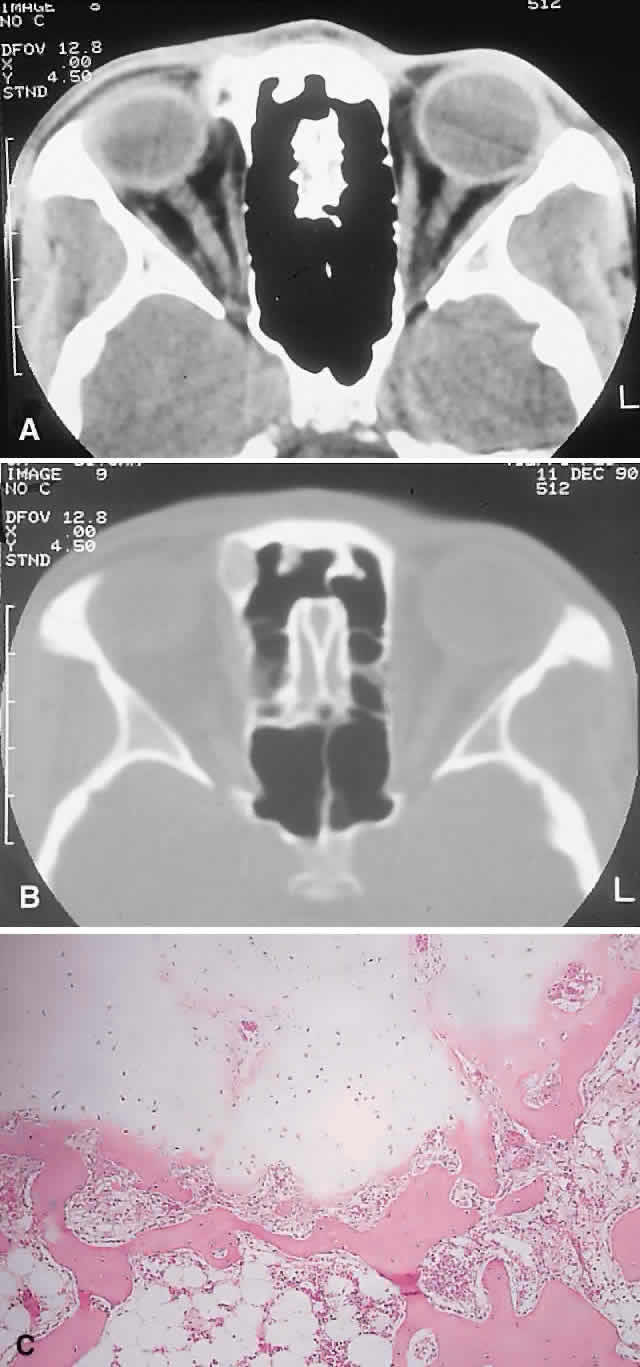

PRESENTATION. The site and the extent of disease are the major determinants of symptomatology. Facial asymmetry, proptosis, and globe displacement evolving over many years are the most common manifestations (Fig. 2). Nasolacrimal duct blockage, diplopia, nasal obstruction, malocclusion, raised intracranial pressure, and cranial nerve palsies also occur.25,28–30 Acute or subacute compressive optic neuropathy can arise as a result of intralesional hemorrhage, sphenoidal mucocele, or secondary aneurysmal bone cyst.31 A more chronic visual loss, although less commonly reported, may occur as a result of compression in the optic canal or at the chiasm. On occasion, a superimposed ischemic neuropathy in the context of chronic compression leads to an acute on chronic deterioration in vision.32

Fig. 2. A. A 20-year-old man presented with a longstanding history of left proptosis and facial asymmetry. B and C. Bone window CT scan showed extensive fibrous dysplasia involving the greater wing of the sphenoid in a sclerotic fashion and a more pagetoid appearance in the maxillary and ethmoidal regions. D and E. Dominant histologic features consisted of irregular trabeculae of woven bone in a fibrous stroma with minimal osteoblastic activity (E) surrounding the osteoid (hematoxylin-eosin; D × 20, E × 50).

IMAGING. In the craniofacial bones, fibrous dysplasia tends to expand the bone, with thinning of the overlying cortex. The margins are poorly defined, and the dysplasia transgresses suture lines; the proportion of mineralized to fibrous tissue determines the degree of radiolucency. Most cases demonstrate a relatively equal mixture, resulting in a pagetoid appearance. Where the fibrous element is predominant, there may be cystlike areas; a preponderance of mineralized tissue, however, results in a homogeneous, sclerotic, “ground-glass” picture. Fries34 reviewed 39 patients with fibrous dysplasia of the craniofacial bones and found a pagetoid pattern to be most common (56%), followed by sclerotic (23%) and cystlike (21%) appearances.